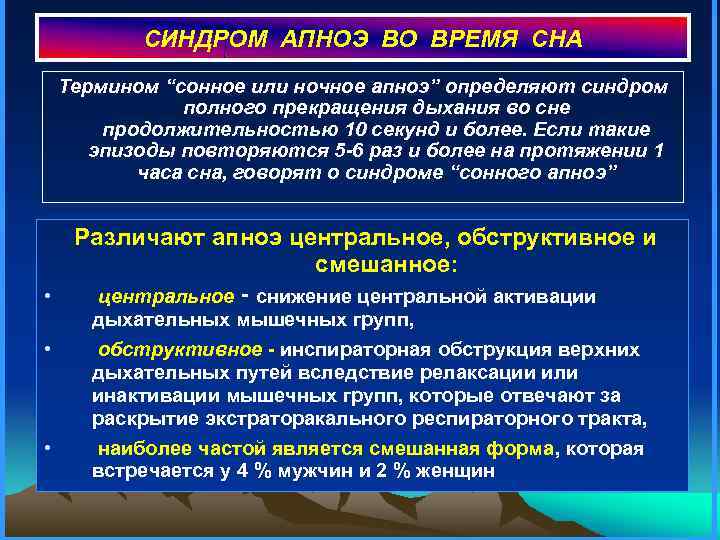

СИНДРОМ АПНОЭ ВО ВРЕМЯ СНА Термином “сонное или ночное апноэ” определяют синдром полного прекращения дыхания во сне продолжительностью 10 секунд и более. Если такие эпизоды повторяются 5 -6 раз и более на протяжении 1 часа сна, говорят о синдроме “сонного апноэ” Различают апноэ центральное, обструктивное и смешанное: • • • центральное ‑ снижение центральной активации дыхательных мышечных групп, обструктивное - инспираторная обструкция верхних дыхательных путей вследствие релаксации или инактивации мышечных групп, которые отвечают за раскрытие экстраторакального респираторного тракта, наиболее частой является смешанная форма, которая встречается у 4 % мужчин и 2 % женщин

СИНДРОМ АПНОЭ ВО ВРЕМЯ СНА Термином “сонное или ночное апноэ” определяют синдром полного прекращения дыхания во сне продолжительностью 10 секунд и более. Если такие эпизоды повторяются 5 -6 раз и более на протяжении 1 часа сна, говорят о синдроме “сонного апноэ” Различают апноэ центральное, обструктивное и смешанное: • • • центральное ‑ снижение центральной активации дыхательных мышечных групп, обструктивное - инспираторная обструкция верхних дыхательных путей вследствие релаксации или инактивации мышечных групп, которые отвечают за раскрытие экстраторакального респираторного тракта, наиболее частой является смешанная форма, которая встречается у 4 % мужчин и 2 % женщин